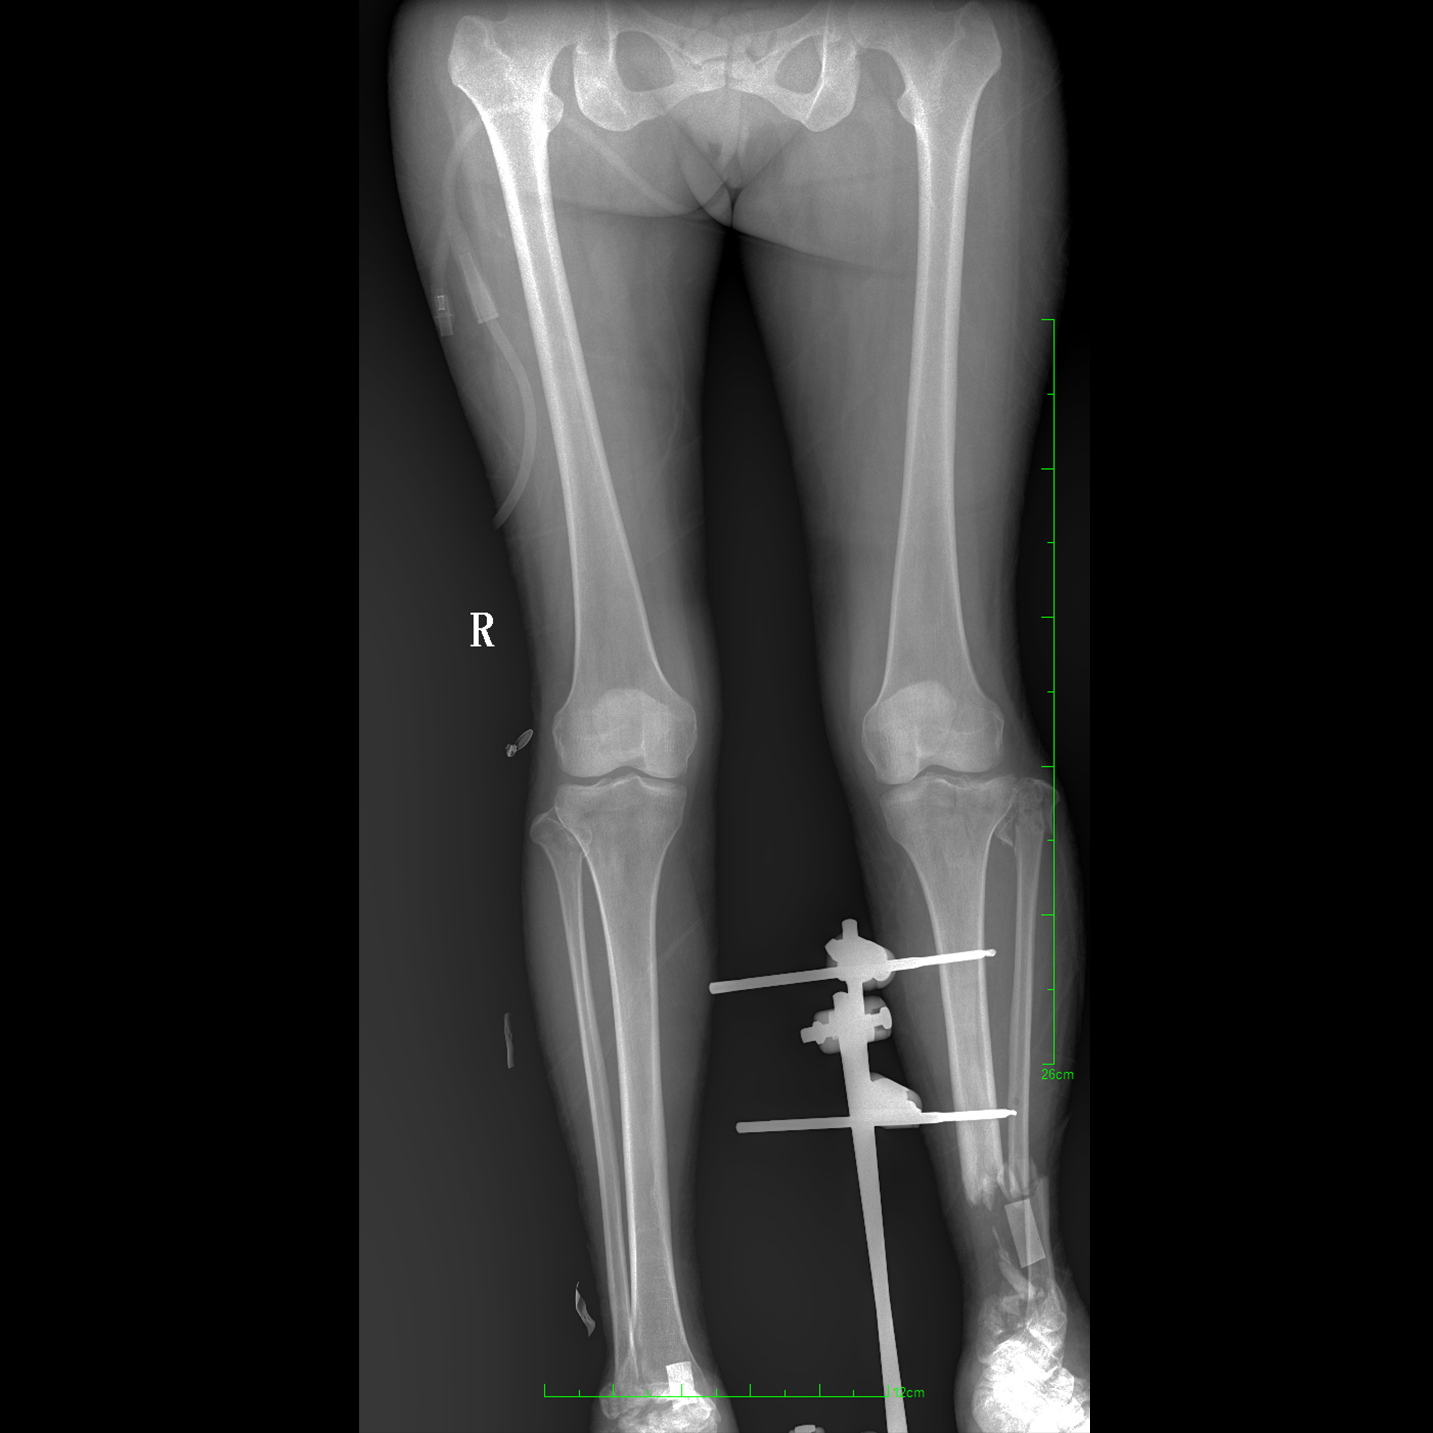

17"*34"有效視野,一次成像不拼接。相較于多張攝影再軟件拼接的DR設(shè)備,PLX8600解決了拼接圖像存在密度不均勻,拼接處圖像配準(zhǔn)和放大效應(yīng)等問(wèn)題,給臨床帶來(lái)了大視野影像解決方案,可一次性覆蓋全脊柱或雙下肢影像。

支持全脊柱攝影、雙下肢攝影、脊髓造影、復(fù)雜創(chuàng)傷、人工關(guān)節(jié)置換、關(guān)節(jié)損傷的修復(fù)重建等大視野臨床應(yīng)用